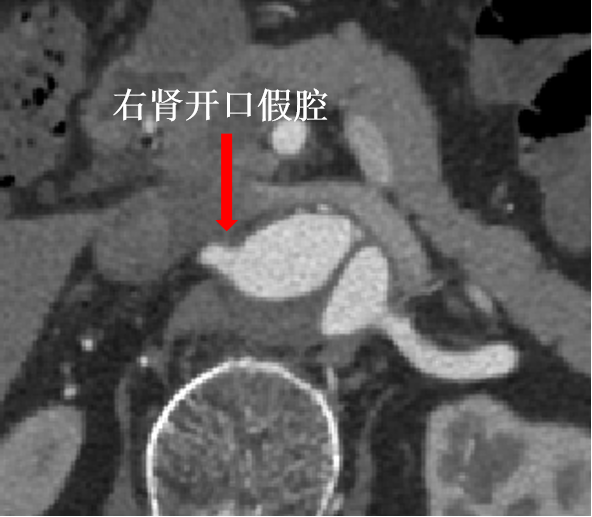

病史:68岁男性,胸腹主动脉夹层动脉瘤三年余,2021年接受B型夹层腔内修复术,术后恢复良好。近期复查发现腹主动脉夹层破口增大,假腔扩张明显。

手术方案:内脏区体外三开窗(CA、SMA、LRA),RRA原位开窗。

预三开窗+右肾原位开窗重建

Fustar+Futhrough原位穿刺破膜

预三开窗+肾动脉原位开窗重建